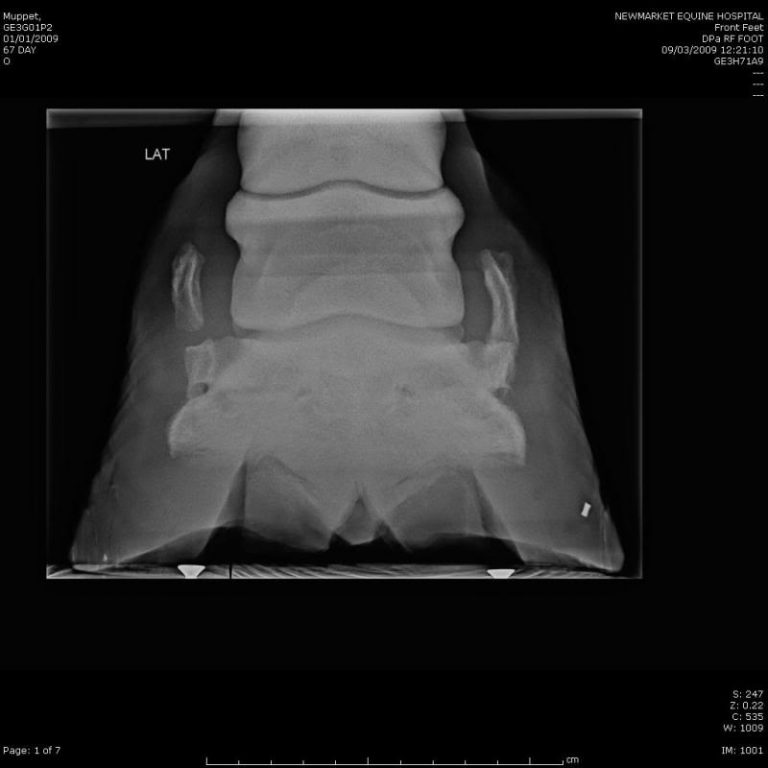

Ossification of the Cartilages of the Foot (Sidebone) Veterian Key What Causes Sidebone In Horses Sidebone usually occurs in the forelimb, cases involving the hindlimb are usually associated with acute trauma or chronic repetitive trauma (such as punctures, chronic bruising. It is most common in the forefeet of heavy horses or of horses with poor conformation. The exact cause of sidebone is unknown, but it may be related to traumatic injury or genetic factors. Although. What Causes Sidebone In Horses.